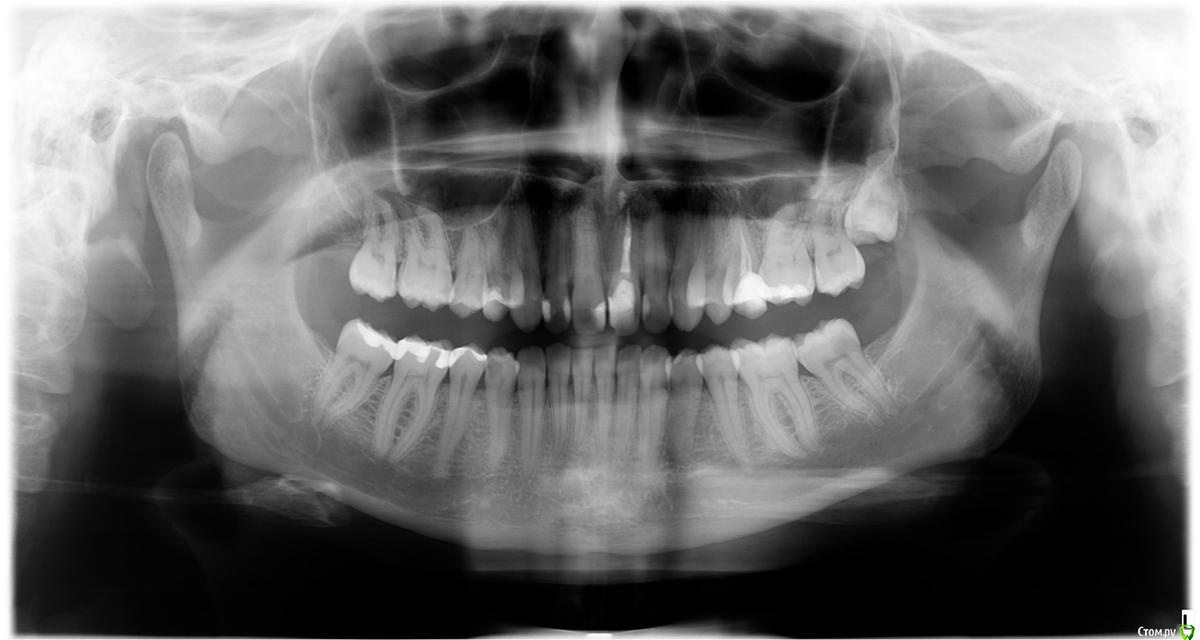

Реза Опубликовано 6 марта, 2020 Автор Поделиться Опубликовано 6 марта, 2020 Посоветуем. Снимок выкладывайте искомой области. Можно фрагмент панорасного. Можно последовательные прицельные.Вот снимок, помогите плиз Ссылка на комментарий

Реза Опубликовано 6 марта, 2020 Автор Поделиться Опубликовано 6 марта, 2020 СделайтеВот снимок, помогите плиз Ссылка на комментарий

DmitrySH Опубликовано 6 марта, 2020 Поделиться Опубликовано 6 марта, 2020 Два варианта.1. Поправить пломбы на зубах 12.22, сделать винир на зуб 11 и коронку на зуб 212. коронку на зуб 21 и виниры 12,11,22 2 Ссылка на комментарий

dok1 Опубликовано 7 марта, 2020 Поделиться Опубликовано 7 марта, 2020 21 - коронка 1 Ссылка на комментарий

Паращук Роман Опубликовано 11 марта, 2020 Поделиться Опубликовано 11 марта, 2020 композит на двойки,на правый центральный винир ,на левый коронка. Ссылка на комментарий